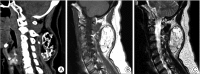

Ossified lipoma or osteolipoma are rarely reported. It is defined as a histologic variant of lipoma that has undergone osseous metaplasia. Osteolipoma presents with a dominant osseous component within a lipoma. We report a case of a histologically confirmed osteolipoma on the nuchal ligament independent of bone. The patient was a 51-year-old female who presented with a 5-year history of a painless, progressively enlarging mass on the posterior neck. Computed tomography and magnetic resonance imaging showed a circumscribed mass compatible with fat between the C2 and C6 spinous processes with a large calcified irregular component. The mass with dual components was totally removed under general anesthesia and no recurrence was observed after 6 months of follow-up. We also reviewed the clinicopathologic features of previously reported osteolipomas in the literature and suggest that although osteolipoma is a rare variant of lipoma, it should be considered in the differential diagnosis when a lipoma of the posterior neck mixed with a bony component is encountered.